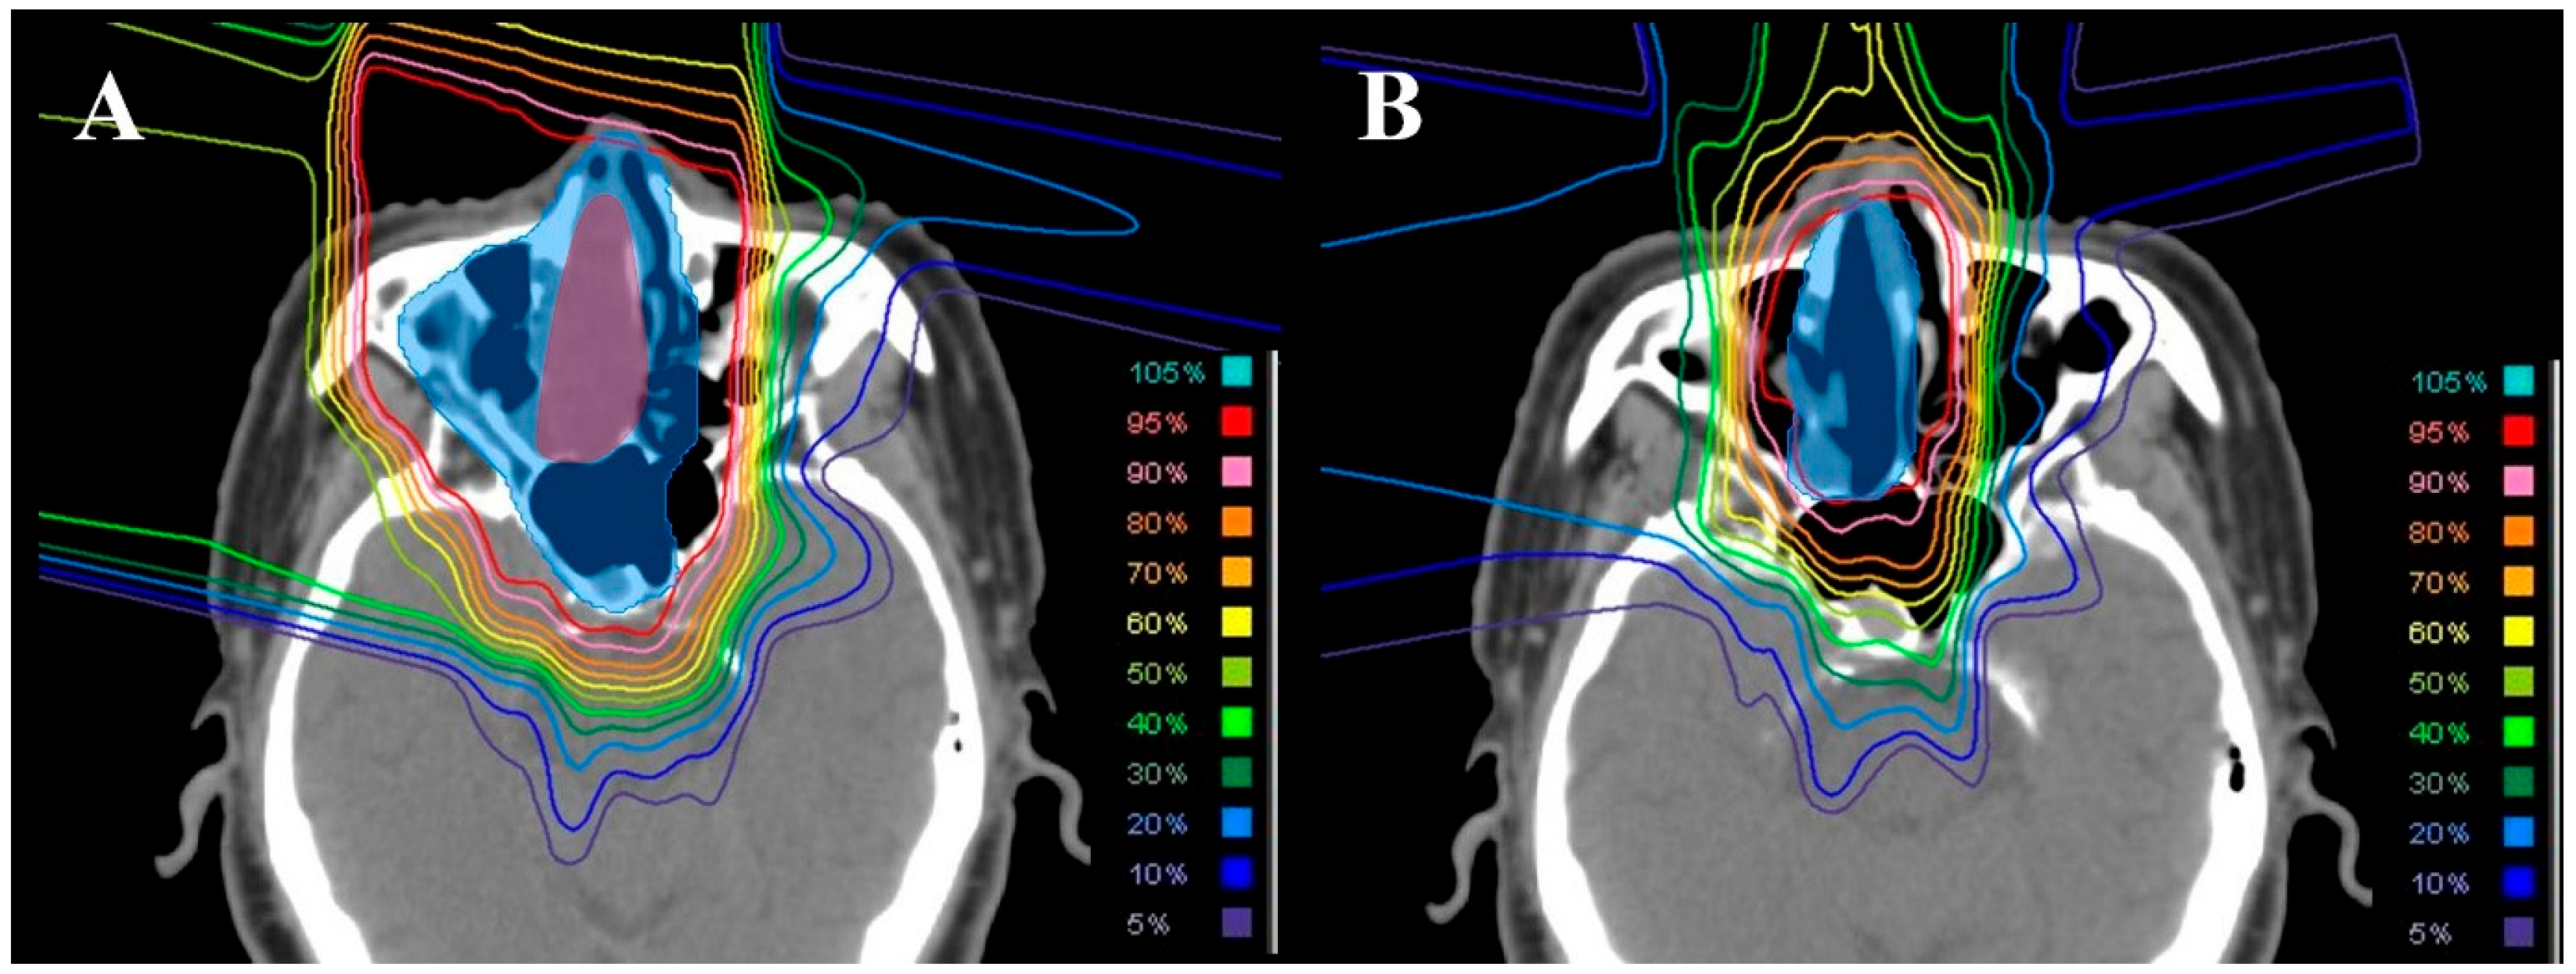

2.2. Dosimetric Comparison with Photon Therapy

3.2. Dosimetric Comparison